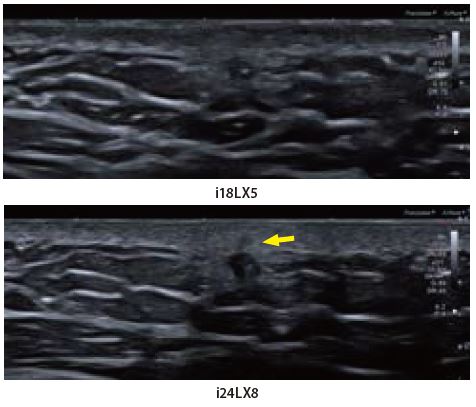

Випадок 2: Інфікована злоякісна виразка шкіри

Безпрецедентна якість доплерівського зображення на i24LX8 в ближньому поліпродемонстрована на цій інфікованій злоякісній виразці шкіри. cSMI і mSMI відображає розгалужену багату гіперваскулярну мережу капілярів з високою роздільною здатністю, яка не може бути виявлена при більш низькій частоті.

Мал. 11.